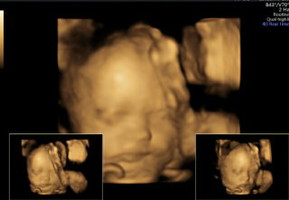

Terima kasih untuk debay yang ada diperut. kuat & mau diajak kerjasama, dari yang gak ketauan hamil masih bolak balik naik turun tangga angkut barang untuk pindahan dari kost ke kontrakan, angkat pasir kucing 20 kilo ternyata lagi hamil 8 minggu, sementara suami angkat yang lebih berat2. UK 16 minggu ngumpet2 dari suami beresin sendiri gudang yang berantakan karena gak enak kalau mertua dateng ke rumah. UK 24 minggu ngerasain ada sesuatu gerak2 di perut, sungguh bahagia!! Makasih malaikat kecilku udah kuat di dalam rahim mama, mau kerja berat, bersyukur gak pernah nge flek dan semuanya sehat2 aja, malahan debaynya kelebiham berat badan setengah kilo dari yang seharusnya. Itu tandanya kamu lebih dari sehat ? #TerimaKasihkuHari1